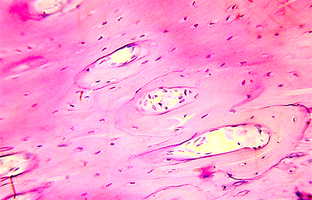

2. Поверхность и структура материала для изготовления биоимплантатов

3. Полный точный химический состав материалов